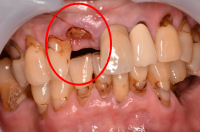

主訴

以前治療した右下の犬歯が、虫歯になり色が変わってきているので、治したい。

治療内容

根管治療をし、オールセラミック冠を被せました。

所感

神経が取り除かれ、歯自体が変色し、虫歯になっていました。根管治療をし、ファイバーコアを入れ、オールセラミック冠を被せました。

オールセラミック冠1本(失活歯):¥104,500(税込)